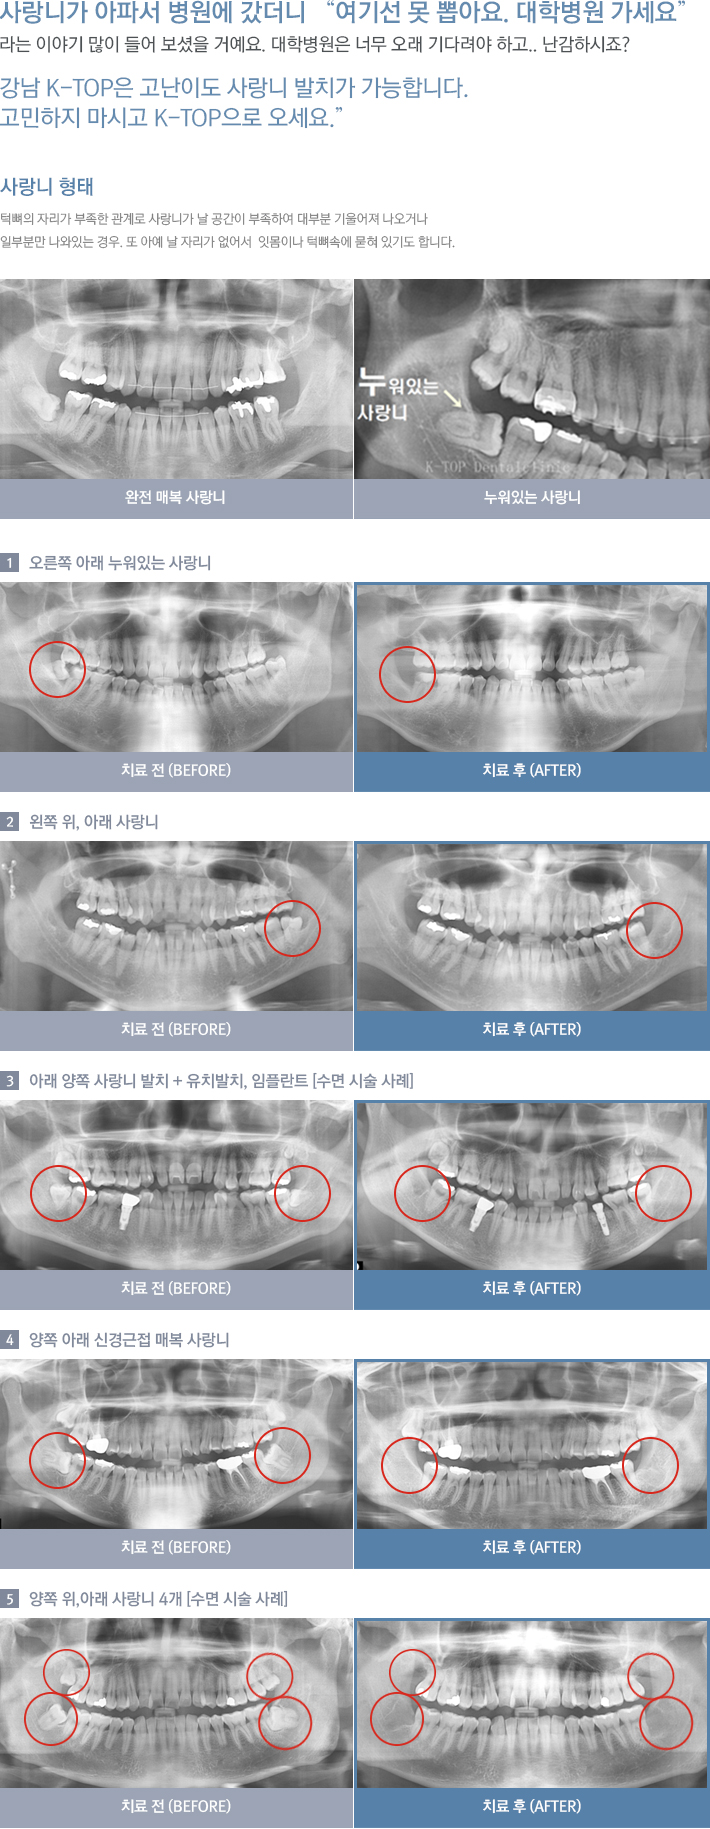

• »ç¶û´Ï ¹ßÄ¡

»ç¶û´Ï ¹ßÄ¡